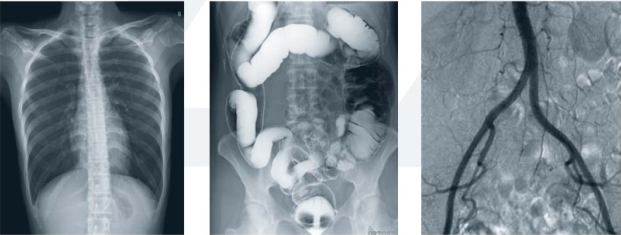

醫用dr設備是一種新的成像技術,可直接將X線光子通過成像板轉換為數字化圖像,實現了模擬X圖像向數字化X線圖像的轉變。主要由X線球管、X線高壓發生器、數字探測器、機械部件和圖像系統等組成。

目前,醫用dr設備的應用越來越普及,市場上的dr設備種類也比較多。主要以所使用的數字影像探測器類型來分類,有采用TFT(thin-film technology薄膜工藝學)技術的平板探測器,其中又分為非晶硒直接轉換探測器和熒光晶體(碘化艷、硫酸釓等)—非晶硅間接轉換探測器,還有熒光晶體—光學系統—CCD/CMOS型DR系統,以及各類線陣掃描型數字成像系統。

3.對骨結構、關節軟骨及軟組織的顯示優于傳統的X線成像,還可進行礦物鹽含量的定量分析;易于顯示縱隔結構如血管和氣管;對結節性病變的檢出率高于傳統的X線成像;在觀察腸管積氣、氣腹和結石等含鈣病變優于傳統X線圖像;體層成像優于X線體層攝影;胃腸雙對比造影在顯示胃小區、微小病變和腸粘膜皺襞上,數字化圖像優于傳統的X線造影。

4.醫用dr設備的成像過程是數字化成像過程。X線探測器將透過人體的X線能量轉換和數字化,包括X線采集、轉換、量化、傳輸、處理、顯示等在內的整個X線成像過程均是數字化信息處理過程。數字化攝影模式改變了圖像信息形成的基礎,X線信號的載體不再是屏/片系統,而是由眾多種類的X線探測器取代,X線探測器通過不同的信號采集原理,把代表人體信息的X線強度分布,采用數字化模式進行采集、轉換、儲存、處理和顯示。